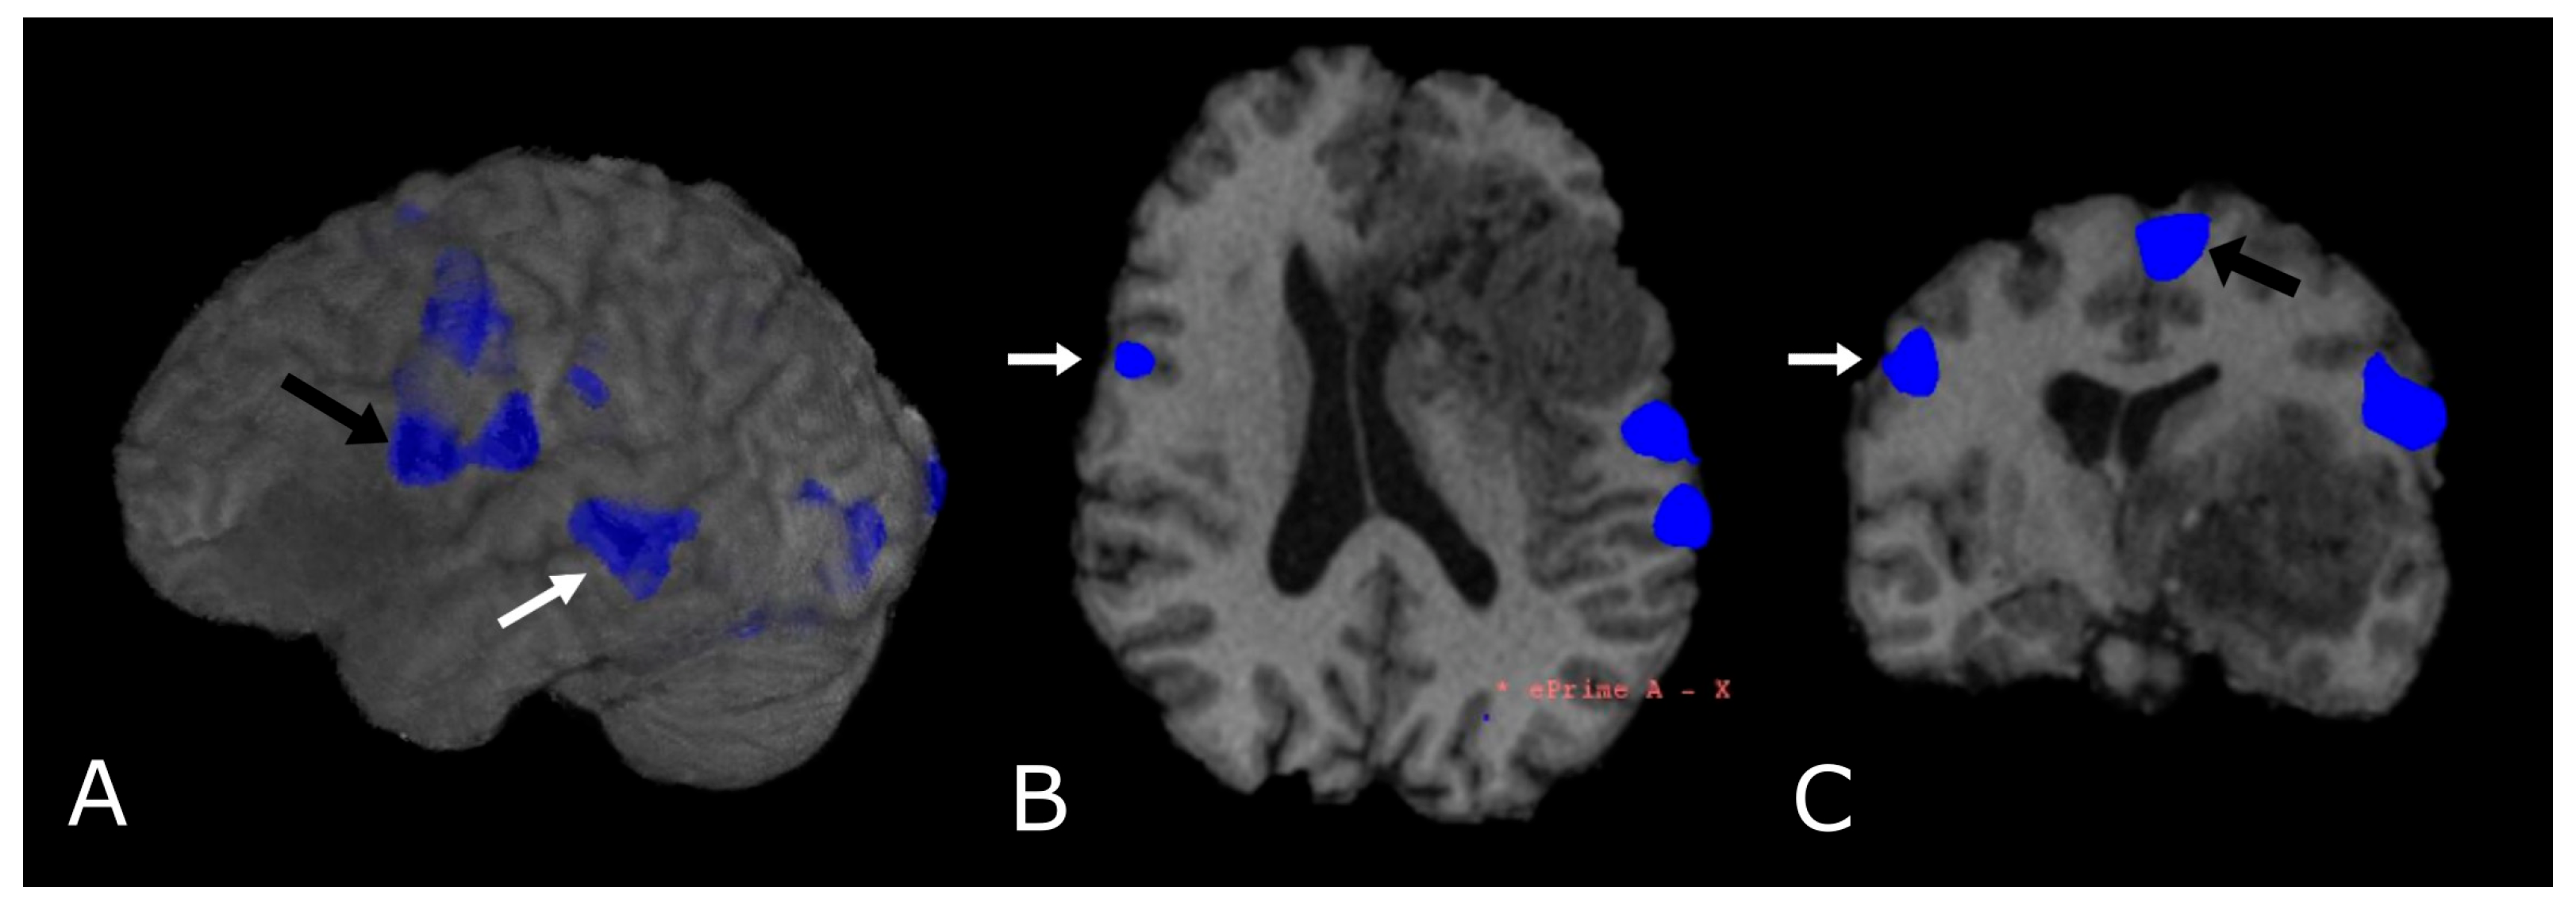

6. Functional MRI